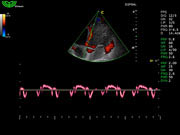

Система поддерживает СFM-режим, PW-режим, CW-режим, режим направленного энергетического потока, режим Color-M, панорамный режим, ECG, DICOM 3.0 и универсальные пакеты программ для кардиологии, сосудистого исследования и акушерства.

Режимы изображения: B, 2B, B/M, B/BC, CFM, PW, HPRF, PD, направленный PD, CW, режим Color M.

Дополнительные возможности: триплекс, трапециидальное отображение, анатомический М-режим, «free-hand» трехмерная реконструкция, авто-доплер.

D3P64L 3.0МГц, фазированная решетка.

2.0МГц – 4.4МГц. Применения: кардиология, брюшная полость, акушерство. |